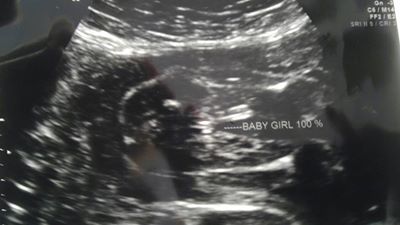

Back from my anatomy scan. Baby is 100% GIRL!!!! I am still in total shock. Super happy, no elated is a better word, lol.

Attachment 11712